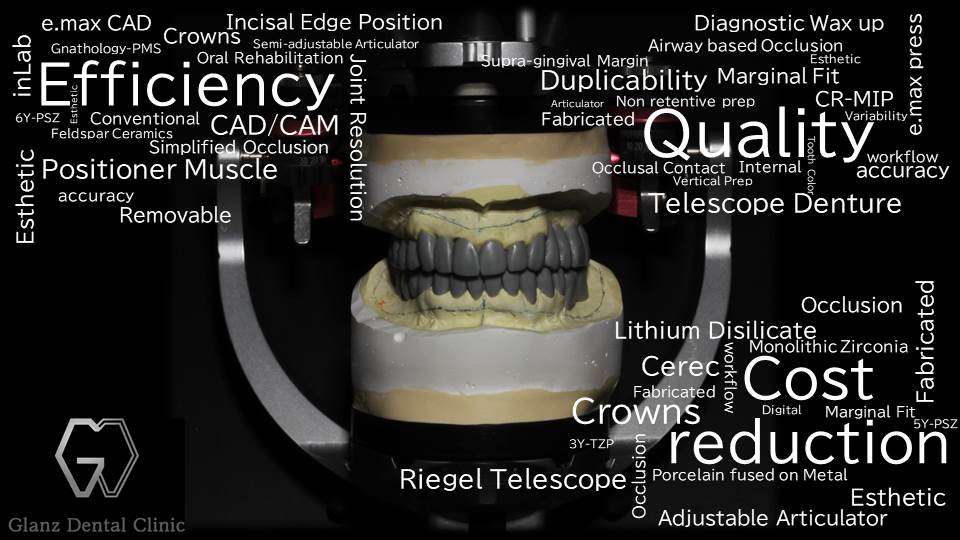

「歯科治療をする度に銀歯が増えてしまう」という経験をしたことはありませんでしょうか?厚生労働省の定める健康保険適用の材料は長らく銀歯が主役でしたが、近年ではインプラントの登場、セラミックス材料や高強度レジン系材料、そして接着性レジンセメント材料の進歩により、その主役は金属修復からCAD/CAMテクノロジーを駆使した最新のデジタル歯科治療用材料に取って代わっています。